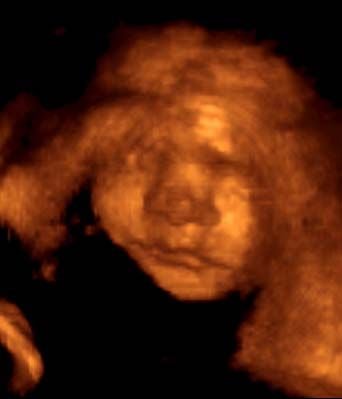

A nyolcvanas években kidolgozott új diagnosztikai módszerek alkalmazása alapvetően új helyzetet teremtett a kora terhesség felismerésében. Egyfelől olyan különlegesen érzékeny immunológiai terhességi próbákat dolgoztak ki, amelyek a tíznapos (!) magzatot is képesek érzékelni. A megtermékenyítést követően az osztódó és a méh felé vándorló magzatkezdemény felszínén hamar kialakulnak azok a sejtek, amelyekből a lepény magzati része lesz. S ezek már a magzati fejlődés első hetének a végén elkezdik termelni azt a lepényhormont (humán koriogonadotropin-t), amely a petefészek sárgatestműködését fokozva megakadályozza az esedékes havivérzés bekövetkeztét. Ez ugyanis végzetes lenne az éppen megtermékenyített petére nézve. A lepényhormon egyik összetevőjének (a béta-alegységnek) a kimutatása kínál lehetőséget a terhesség felismerésére már a fogamzást követő tizedik napon. Tehát még ki sem maradt a havivérzés, és már megállapítható a terhesség!Az ilyen új típusú terhességi próbák forradalmi változást hozhatnak majd a kora terhesség felismerésében és védelmében. Egy baj van csak, mint általában az új módszerekkel, és ez a terhességi próba költségessége. Szerencsére hazánkban Pácsa Sándor, a Pécsi Orvostudományi Egyetem kutatója, aki az immunológiai diagnosztikai módszerek világszerte elismert szakértője, képes volt ennek a vizsgálati technikának a hazai alkalmazását megoldani. Igy az OCsM-ben részt vevőknek fel tudjuk ajánlani, hogy ha kívánják, már az első kimaradt havivérzés időszakában – akár annak első napján – tájékoztatjuk őket e próba segítségével a terhesség fennállásáról vagy éppen hiányáról. Remélhetőleg hamarosan széles körben alkalmazásra kerülhet ez az új megoldás.Már a terhesség e korai időszakában hasznos az ultrahangvizsgálat is, mely megerősítheti a kora terhesség fennállását, és lehetővé teszi az úgynevezett fantomiker-jelenség tanulmányozását.